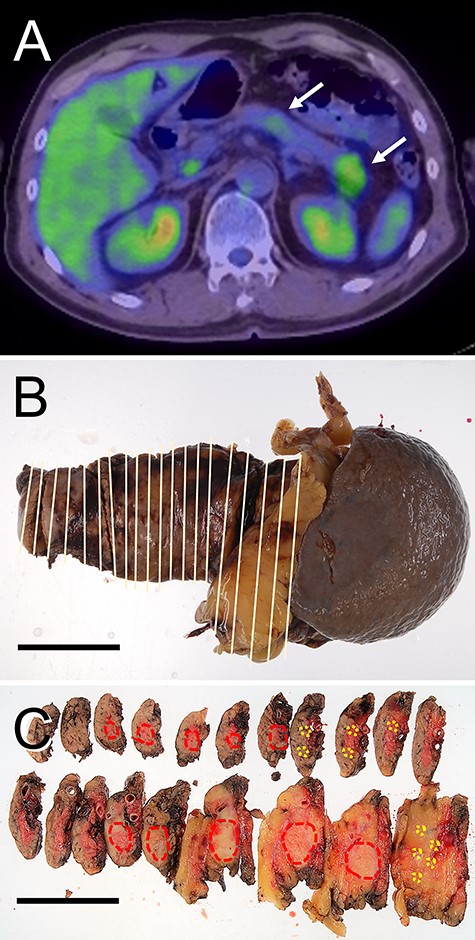

Radiological features and macroscopic findings of Case 2. (A) FDG-PET: two nodular masses with high SUV were detected in the pancreas (white arrows). (B) Macroscopic finding of the resected pancreas. (C) Two nodular lesions (red circles) and foci of small lesions (yellow circles) were indicated on the cut surface.

A nodular mass was noted in the body or tail of the pancreas by USG in three cases (Figs 1–3). Endoscopic ultrasound-guided fine needle aspiration gave negative result in all patients. No lesion was detected by computed tomography (CT) (Fig. 1B and Table 1). Low-intensity mass was detected in the body or tail with T1-weighted imaging of magnetic resonance imaging (MRI: Fig. 1C and Table 1). 18F-fluorodeoxyglucose positron-emission tomography (FDG-PET) detected two lesions with high standardized uptake value (SUV) in the body and tail in Cases 1 and 2 (Figs 1D and2A and Table 1) and one lesion in the body in Case 3 (Fig. 3A and Table 1). In the resected pancreas, two lesions were found in the body and tail of the pancreas in Cases 1 and 2 (Figs 1F and2C, red circles) and one lesion of the pancreatic body in Case 3 (Fig. 3C, red circles). Small foci of lymphoid hyperplasia were noted in all cases (Figs 1F, 2C and3C, yellow circles).

Radiological features and macroscopic findings of Case 3. (A) FDG-PET. (B) Macroscopic finding of the pancreas. (C) A nodular lesion (red circles) and foci small lesions (yellow circles) were indicated on the cut surface.